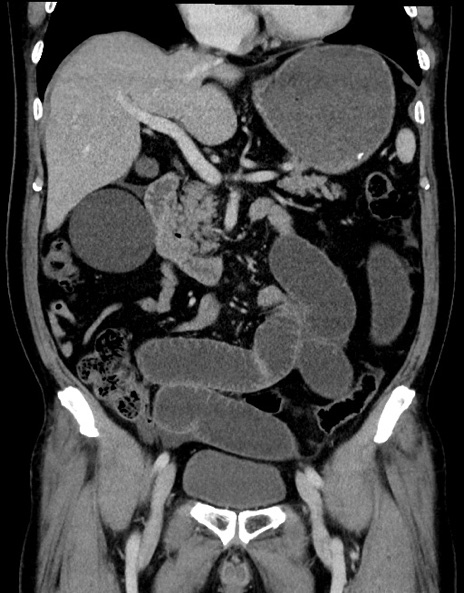

症例15(冠状断像)

【症例】70歳代男性

【主訴】腹痛

【現病歴】今朝から腹痛あり。全体的に痛い。特に左上の方。排ガスが今日はない。冷や汗が出る。

【既往歴】直腸癌術後

【身体所見】左側腹部〜上腹部に圧痛あり。腹膜刺激症状明らかなではない。軽度反跳痛。左下腹部に術後瘢痕あり。

【データ】WBC 7700、CRP 0.02